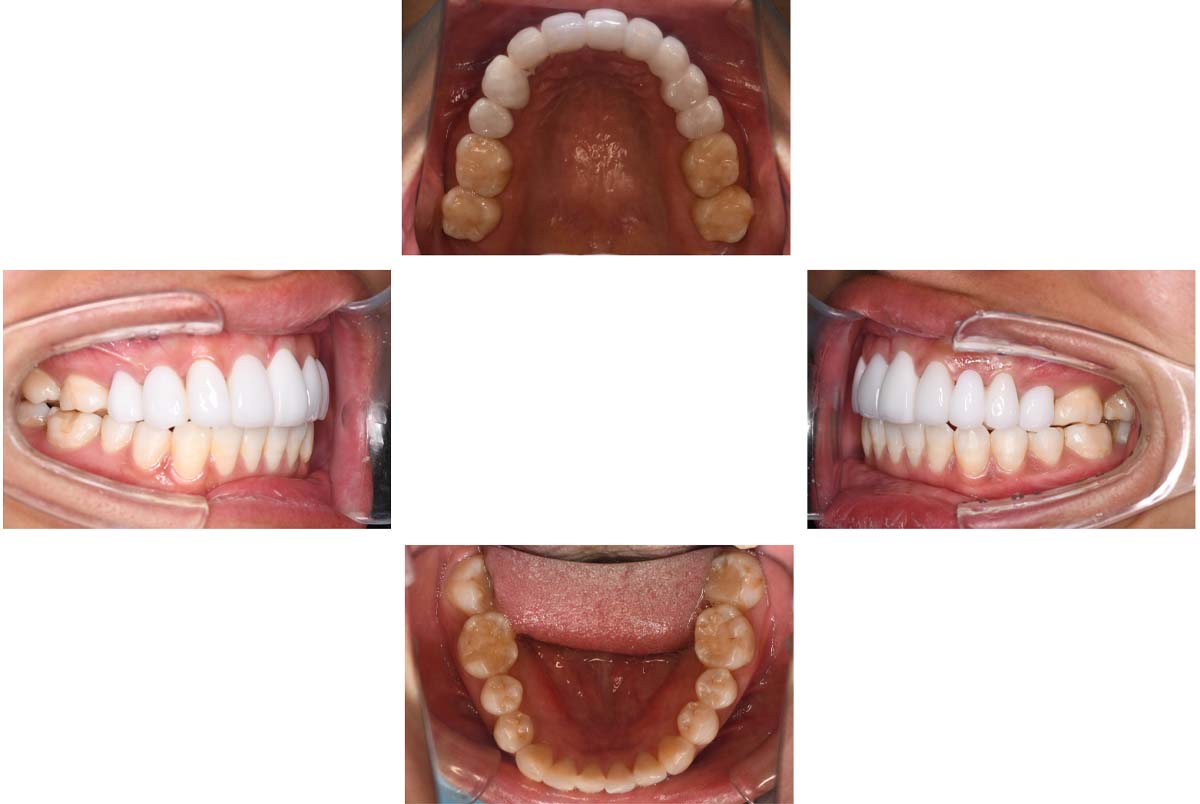

| 治療内容 | ①スプリントを装着 ②副子を装着 ③2024年4月 口腔内反映開始 ④副子を入れた状態の所まで咬合を挙上 (バイトアップ) ⑤2024年5月 上顎前歯部8本へ仮歯(TEK) を装着 |

バイトアップ後